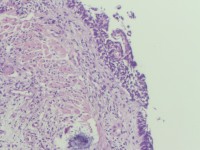

咔血3月,纤维支气管镜:右侧肺下叶基底段黏膜增生。能诊断肺部鳞状细胞癌吗?

鳞癌。